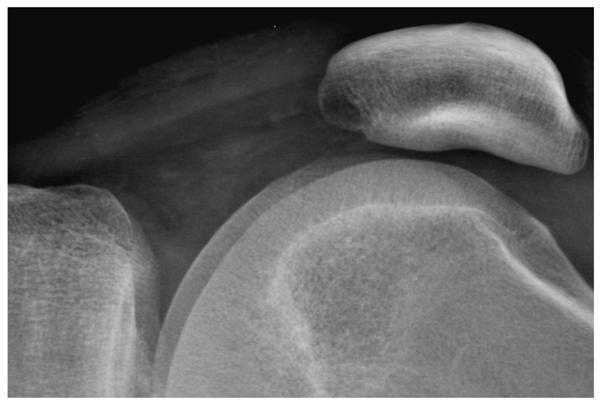

When the edge restoration filter is appropriately specified, fine detail has a realistic appearance and the image will not have excessive noise. This is illustrated in figure 3 for a lateral knee view recorded using a CR system with a high-resolution phosphor screen. Inappropriate specification of the restoration filter can lead to artifacts. In some systems of earlier design, filters were implemented using spatial convolutions based on a small kernel that were not able to amplify image components with low and intermediate spatial frequencies. These were often applied with excessively high gain. This over-amplification of high spatial frequencies causes edge artifacts appearing as an oscillating signal that is sometimes referred to as ‘edge ringing’.

Figure 3a. A digital radiograph of the knee taken with a high resolution CR screen (HR screen, Eastman Kodak Company) is illustrated using display processing with no edge restoration.

Figure 3b. The knee radiograph shown in figure 3a is illustrated using display processing with edge restoration.